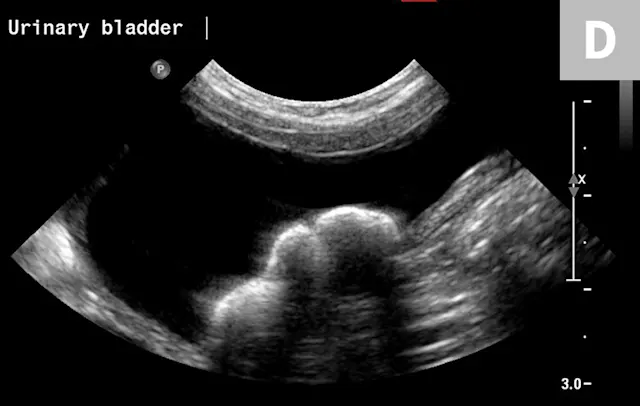

Clinical signs associated with ureteral calculi may range from chronic non-specific signs to acute or chronic renal failure. The presence of hydronephrosis can be highly suggestive of a ureteral obstruction (Figure 6).

FIGURE 6A

1 / 2

Mild to moderate right hydronephrosis and proximal ureteral dilation in a Dalmatian.